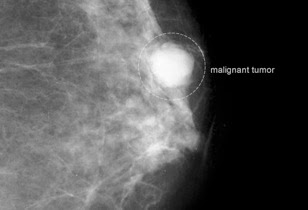

Καρκίνος του μαστού

Όσο νωρίτερα διαγνωστεί ο καρκίνος του μαστού, τόσο υψηλότερα είναι τα ποσοστά επιτυχούς θεραπείας. Εάν βρεθεί σε αρχικό στάδιο είναι μικρότερες οι πιθανότητες ο καρκίνος να έχει επεκταθεί στους λεμφαδένες και σε ζωτικά όργανα όπως οι πνεύμονες και ο εγκέφαλος. Στις ηλικίες των 20 και των 30 ετών, ο έλεγχος των μαστών πρέπει να συμπεριλαμβάνεται στο τακτικό σας check up, κάθε 1-3 χρόνια, ή και συχνότερα εάν υπάρχουν άλλοι παράγοντες όπως το βεβαρημένο ιστορικό που το απαιτούν. Ο Υπέρηχος Μαστού είναι μία διαγνωστική μέθοδος ανώδυνη και ακίνδυνη (δεν υπάρχει κανενός είδους ακτινοβολία) και μπορεί να επαναλαμβάνεται όσο συχνά χρειάζεται άφοβα. Αφορά τη χρήση υπερήχων για τον πλήρη έλεγχο του μαστού και της μασχαλιαίας χώρας (έλεγχος λεμφαδένων αυτής). Σε ηλικίες άνω των 40 ετών κάθε χρόνο απαιτείται μαστογραφία. Βέβαια την συχνότητα με την οποία θα πρέπει να ελέγχονται οι μαστοί σας θα την καθορίσει ο γιατρός σας ανάλογα με το ιστορικό σας.